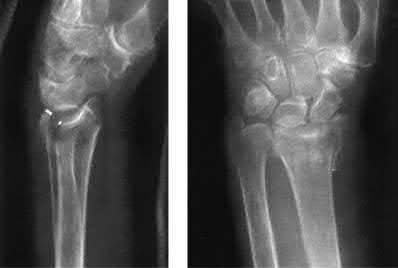

A 64-year-old woman is thrown off a horse, sustaining the injury shown in Figures A and B. She undergoes surgical fixation as seen in Figures C through E. What is the most commonly reported complication of this procedure?

The patient in the scenario has a 2-part proximal humerus fracture treated with a locking plate as seen in Figures A-E. The most common complication with the use of this implant is screw penetration. The terms screw cut out and penetration are often used interchangeably in the literature with cut out appearing more frequently in reports regarding intertrochanteric fractures.

Owsley et al retrospectively reviewed 53 proximal humerus fractures treated with locking plates and the same post-operative protocol. The most common complication was screw cut out or penetration, followed by varus displacement. They concluded that 3 and 4-part fractures in patients over 60 years have a higher incidence of failure.

Agudelo et al retrospectively reviewed 153 patients at a level-one trauma center treated with proximal humerus locking plates, investigating modes of failure for the implant. They determined that varus malreduction (head-shaft angle